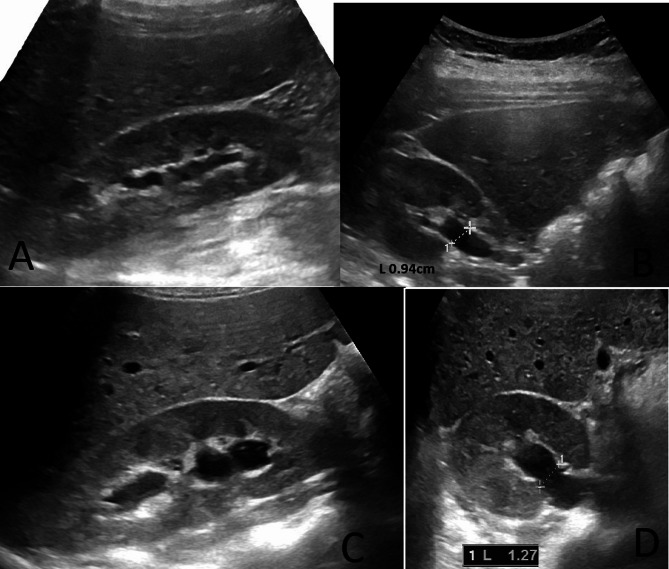

Hydration-induced hydronephrosis in healthy adults: a diagnostic pitfall in renal ultrasound imaging.